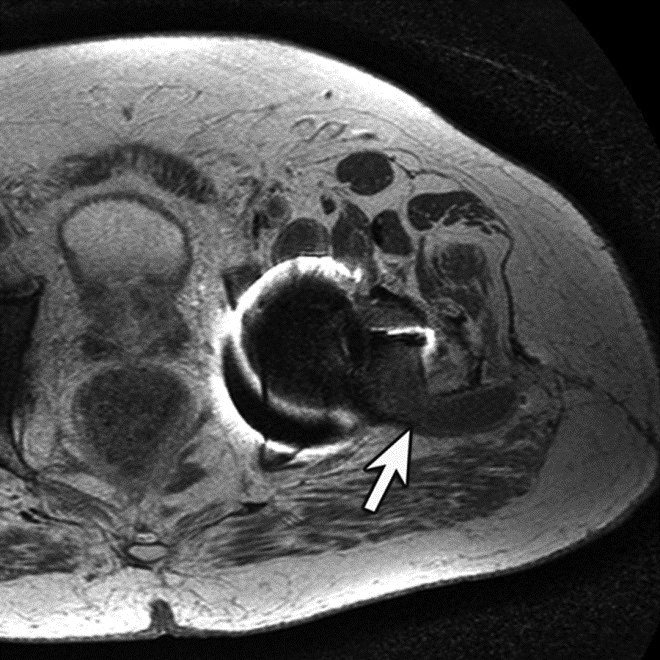

| Inversion Recovery Imaging. (B) Axial STIR MR image in the same patient reveals fluid-signal pseudotumor (arrow) adjacent to the left greater trochanter, which was obscured on prior examination. |

Adverse reaction to metal debris with posterior pseudotumor. Axial T1-weighted fast spin echo (FSE) (A) and STIR (B) MR images demonstrate left peritrochanteric fluid collection (arrow in A and arrowheads in B) arising from the left hip joint in a patient with metal-on-metal hip arthroplasty. Note the thin low T2 signal rim surrounding the fluid collection representing metal deposition. |